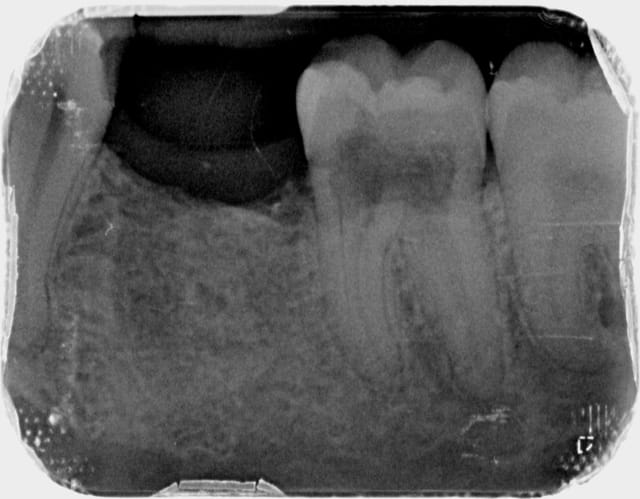

dent asymtomatique,je pense qu'il faut faire l'endo pour stopper le processus,le plancher ne semble pas perforé.

cette conduite vous parait-elle la bonne?

Vérifie quand même qu'il n'y ait pas une carie sous gingivale au collet, lingual ou vestibulaire, ça montre le même type d'image.

Sinon, oui, endo.

oui il faut tenter l'endo pour une résorption interne, mais je ne donne pas cher de la peau de cette dent. On ne voit rien sur la radio, mais il y a de très fortes chances à ce stade de résorption pour qu'il y ait perforation en sous gingival.